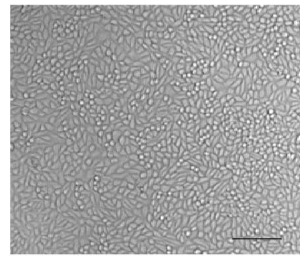

The MDA-MB-468 cell line is a widely used model for TNBC. MDA-MB-468 cell line has a modal chromosome number of 64, though the actual number can vary from 60 to 67 in different cells. It is a cell line with epithelial morphology that have wide applications in breast cancer and immuno-oncology research.

Fig.1 Breast cancer cell MDA-MB-468.Fig.1 MDA-MB-468 cells.1

1. Ayob, Zahidah, et al. "Cytotoxic activities against breast cancer cells of local Justicia gendarussa crude extracts." EvidenceBased Complementary and Alternative Medicine 2014.1 (2014): 732980. Distributed under Open Access license CC BY 4.0, without modification.